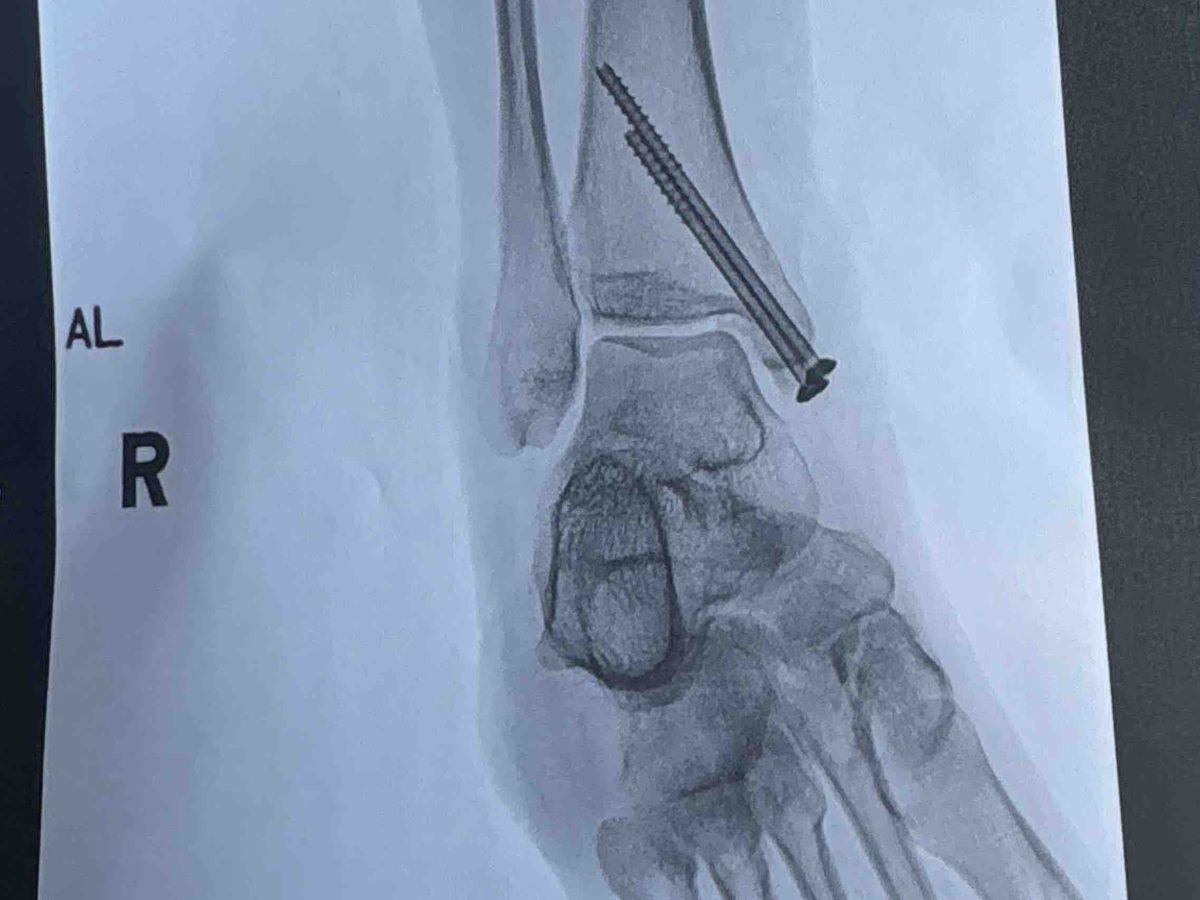

My car was immediately deemed totaled. I had just bought the car with cash only 3 months ago, but that isn’t what I am creating this for. The emts cut my pants because I had a deep to the bone laceration. I had then got into the ambulance and to Halifax I went. I could barely move my right leg especially ankle, was veryyy bruised / swollen. After some x rays what I had hoped was not the case in fact was. Three fractures in my right ankle as well as a fractured patella inside the laceration.. resulting in surgery + 2 screws in my ankle for life + 8 stitches on ankle, 12 stitches on knee and 2 inside knee.